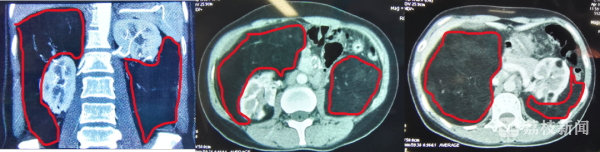

“患者之所以吃不下饭,是因为瘤体巨大压迫腹腔胃肠道,导致食欲不振,除了胃肠道,由于瘤体还压迫到了腰部肌肉及神经,患者来的时候腰部疼痛明显,难以直立行走,整个人非常消瘦,营养状况堪忧!”该院泌尿外科主任、主任医师徐彦教授为王女士做了详细检查,明确诊断为“双侧肾脏巨大错构瘤”。他指着王女士的腹部CT影像继续介绍,“患者的整个腹腔几乎被异常巨大的瘤体占满,肾脏被压迫得就像一个被包裹起来的‘枣核’,肝脏、脾脏也被瘤体挤压错位变形,双侧瘤体甚至延伸到盆腔。”徐彦主任表示,像这样巨大的双肾多发性巨大错构瘤十分罕见,由于压迫到多个脏器,造成相关系统器官功能受损,且出血风险极大,必须尽快手术切除,否则一旦发生破裂,患者有生命危险。